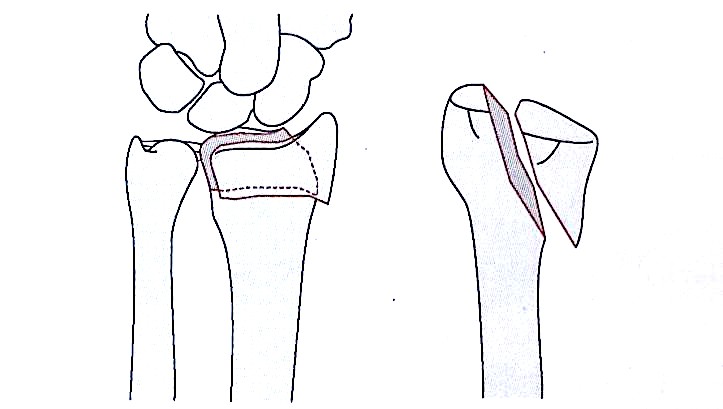

Закрытое восстановление с последующим чрескожным закреплением и фиксацией полезно при переломах дистального радиуса с метафизарной нестабильностью или простыми внутрисуставными переломами.

Первым шагом является анатомическое перемещение, а затем стабилизация обеспечивается грамовыми булавками. Обычно первый штифт передается от радиального стилоида к радиальному метафизом, медиальному в диафиз.

Минимум 2 штифта используются для обеспечения адекватного стабильного перепозиции в ортогональных и боковых положениях, и при желании можно закрепить лунную аспекту.

Внутренняя закрепление (техника Капанджи) обеспечивает дорсальную поддержку. Послеоперационная иммобилизация в шине применяется в течение 2 недель для контроля вращения и минимизации раздражения штифта, после чего ее можно заменить на мягкий лист предплечья.